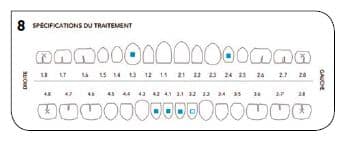

Une fois cette première série d’aligneurs terminée, il a été décidé d’améliorer la position des incisives mandibulaires et de fermer la béance résiduelle (Fig.8).

Fig.8 : Spécifications du traitement.

Pour cette partie du traitement : plus de stripping, moins de taquets (mais plus répartis sur les dents du bas pour le mouvement d’ingresion) et une série de 7 aligneurs supplémentaires (Fig.9 et 10).